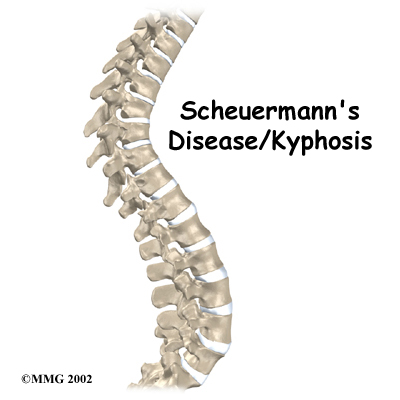

The section of spine from below the neck to the bottom of the rib cage is called the thoracic spine. From the side, the thoracic spine appears slightly rounded. Its shape is like the letter "C" with the opening of the “C” facing the front of the body. This normal curve is called a kyphosis. With an excessive kyphosis, the thoracic spine takes on a hunchbacked appearance.

Scheuermann's disease (also called Scheuermann's kyphosis) is a condition that usually starts in childhood. It affects less than one percent of the population and occurs mostly in children between the ages of 10 and 12. It affects both boys and girls with a slightly higher number of boys affected. Those who do not receive treatment for the condition during childhood often experience back pain as an adult from the spinal deformity. In some cases Scheuermann’s disease doesn’t develop until adulthood.

The angle of normal kyphosis in the thoracic spine varies. The angle increases slightly throughout life both in women and men. During the growth years of adolescence, a normal curve measures between 25 and 40 degrees. In general, kyphosis tends to be more exaggerated in girls. If the curve angles more than 40 degrees in either boys or girls, doctors consider the kyphosis a deformity. Scheuermann's disease causes the thoracic kyphosis to angle too far (more than 45 degrees).

In Scheuermann's disease, the front of the vertebral body becomes wedge-shaped, possibly from abnormal growth. This produces a triangular-shaped vertebral body, with the narrow, wedged part closest to the front of the body. The wedge creates a larger bend in the kyphosis of the thoracic spine.

Scheuermann’s disease usually produces kyphosis in the middle section of the thorax (the chest), between the shoulder blades. Sometimes, however, it can cause kyphosis in the lower part of the thoracic spine, near the bottom of the rib cage.